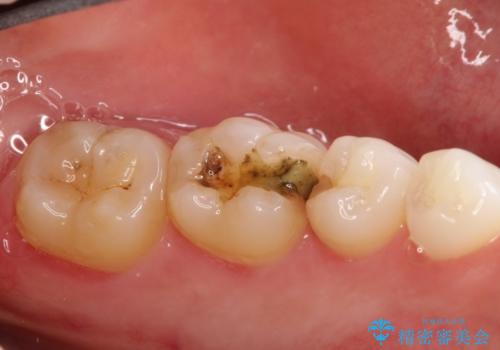

詰め物が外れた セラミックによる精密な修復

- 金属の詰め物がはずれてしまったので、精度の良いセラミックをいれたいのとのこと来院されました。

セラミックインレーにて治療することとなりました。

拡大鏡を使用して精度の高いインレーを装着しました。